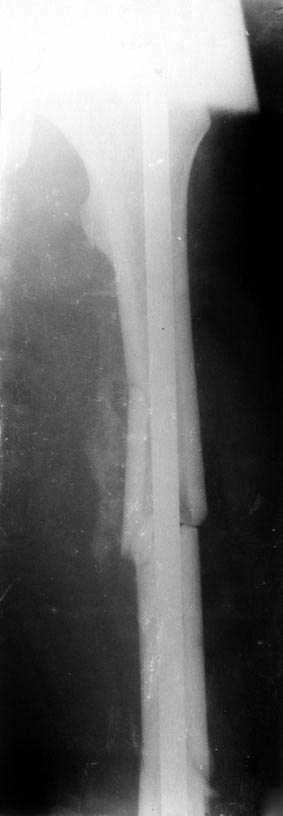

Сегментарный перелом бедра

Пациент (близкий родственник моего компаньона), мужчина, 19 лет, в результате автотравмы получил открытый оскольчатый перелом диафиза левого бедра.

Произошо это где-то 21-22 мая. Примерно 16 июня был проведен остесинтез стержнем в Ставропольском крае. К сожалению, мы об этом обо всем узнали слишком поздно. Вопросы следующие: 1. как вы оцениваете результат операции? (не в смысле критики врача, об этом речи нет, а в смысле понять ситуацию и прогноз) 2. Родственники сейчас осознали проблему и заинтересованы в хорошем исходе лечения. Поэтому вопрос - нужно ли что-либо предпринимать экстренно или ждать консолидации и потом уже что-то думать. Пациент хочет получить хороший функциональный результат, он курсант школы милиции, спортсмен.

Гвоздь не заперт и коротковат в дистальном фрагменте, поэтому нагружать рано не надо, чтобы не телескопировались отломки. Исходя из предположения, что сделано закрыто, первые месяца два ограничиться осторожными движениями в коленном суставе до прямого угла (свешивать ногу с горизонтальной поверхности, обеими руками фиксируя бедро с передней поверхности на уровне дистального отломка), ходить с костылями

без нагрузки на эту ногу. Ну а после снимков в 2 мес. оценить, как дела, и решить с нагрузкой.

Что-то уж больно похоже, что все-таки после открытой репозиции промежуточный отломок на верхнем переломе был привязан к своему ложу...

В случае открытой репозиции шансы на неприятности типа замедленного сращения, несостоятельности фиксации, контрактуры коленного сустава еще выше. То есть мотивация к закрытой смене стержня на запираемый еще больше. Если такой вариант, конечно, доступен. Если нет - как уже говорилось, брэйс или гипсовая повязка. Или на скелетном вытяжении провести недель 6 минимум.